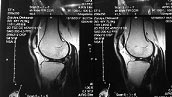

большеберцовой кости. Сделано МРТ коленного сустава, признаки

остеомиелита надколенника с затеком по ходу собственной связки надколенника.

Диагноз: Остеомиелит верхнего полюса левого надколенника с формированием

затека по ходу собственной связки.